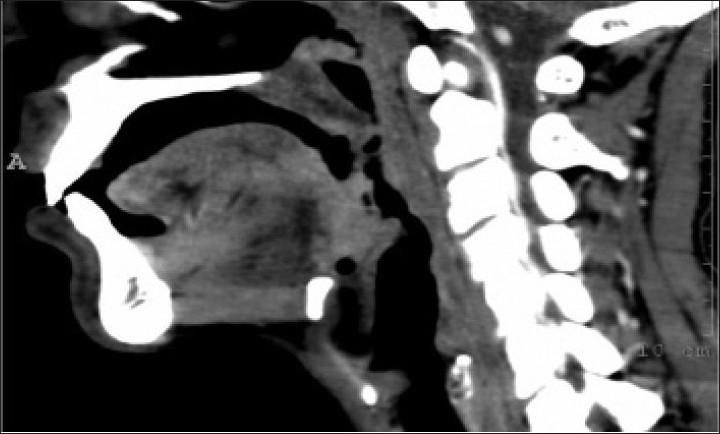

复发性鼻硬结病罕见病例的气道管理

Airway management of an unusual case of recurrent rhinoscleroma.

Rhinoscleroma is a rare entity encountered in anesthesia practice. We discuss the management of a patient after its recurrence, involving the upper respiratory tract i.e. nasopharynx and oropharynx, which compromised the airway. The pateint was referred for anesthesia on three different occasions with different presentations owing to the recurrence of symptoms.The presence of an oropharyngeal membrane with a small opening made airway management a challenge. The patient was successfully managed on all three occasions. Imaging facilitated assessment and subsequent airway management.

摘要

鼻硬结病是麻醉实践中遇到的一种罕见病症。我们讨论了一名患者复发后涉及上呼吸道即鼻咽和口咽的处理情况,这对上呼吸道造成了损害。由于症状复发,该患者在三个不同场合因不同表现被转诊接受麻醉。口咽膜存在且有一个小开口使得气道管理成为一项挑战。该患者在所有三次场合均得到了成功处理。影像学检查有助于评估及后续的气道管理。